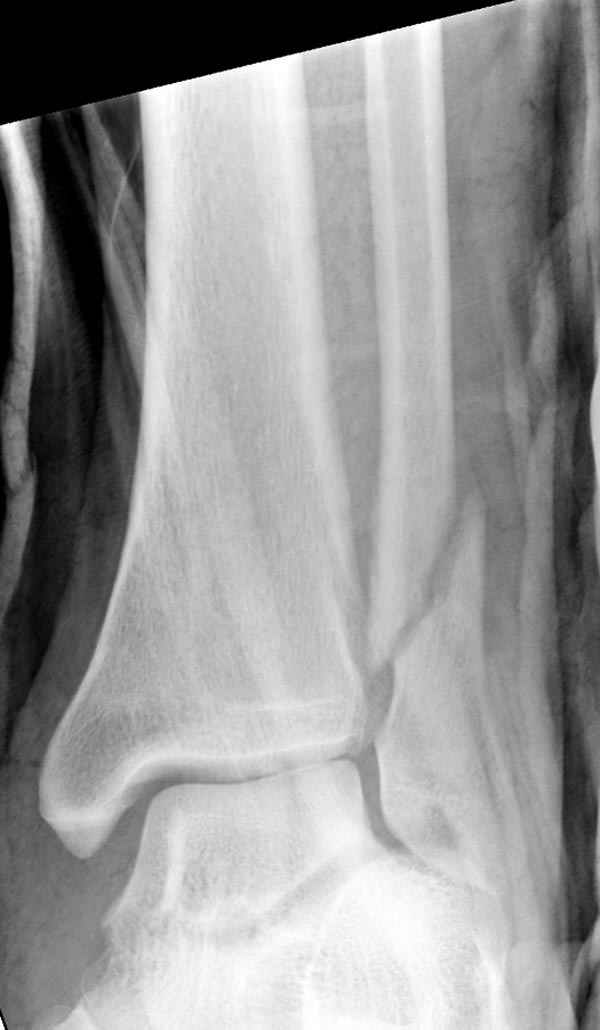

Тему неоднократно разбирали (см. архив), как всегда, недостаточны ренгенологические исследования - кроме прямого и боковых снимков, еще нужна косая ренгенограмма для определения ankle mortise, без мортиз снимка трудно определить высоту и ротацию малоберцовой. (снимки)

Ренгенология даст ответ как классифицировать перелом, на сегодня применяется классификация “Lauge Hansen fracture classification SER supination-external rotation или supination-eversion classification Danis

Weber А, В, С.”

Показания для фиксации: укорочения и ротация малоберцовой, особенно обращают внимание на любой подвывих таранной кости: неустраненый подвывих впоследствии приводит к раннему артрозу. Задний край фиксирует тогда, когда перелом составляет около 25% суставной поверхности голеностопного сочленения и смещение более 2мм.

По снимку ваш случай относится к Weber В, фиксацию производят восстановлением длины малоберцовой кости, под ренгеном (ЭП)контролем, для этого я предпочел бы латеральный доступ, остеотомия по линии перелома, удлинение малоберцовой засчет скоса линии остеотомии, компрессия “lag technique”по линии остеотомии и фиксацию провести латеральной пластиной. Отдельный задний доступ, остеотомия по линии перелома, репозиция и фиксация заднего края вашим предпочтительным методом: 3.5мм шурупом с шайбой или пластиной Antiglide Butress